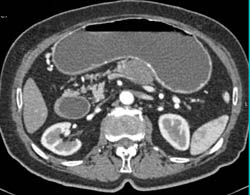

Gastric Carcinoma